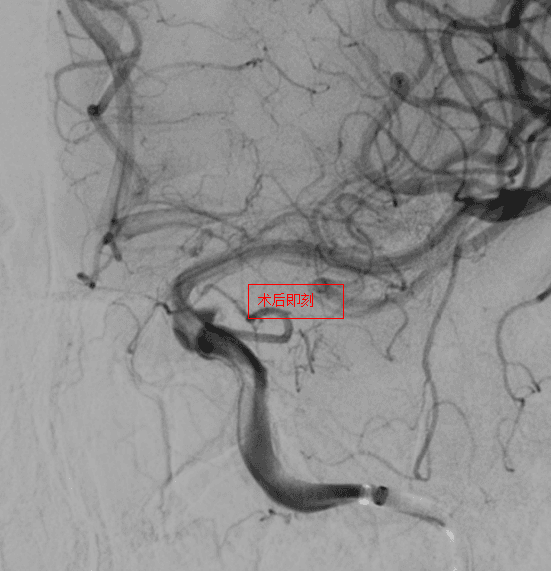

第三例患者确诊为后交通动脉瘤伴近端血管狭窄,双重病变增加了手术难度。团队选择合适尺寸血流导向装置,支架完美打开,即刻动脉瘤内出现造影剂滞留,患者术后2天出院。